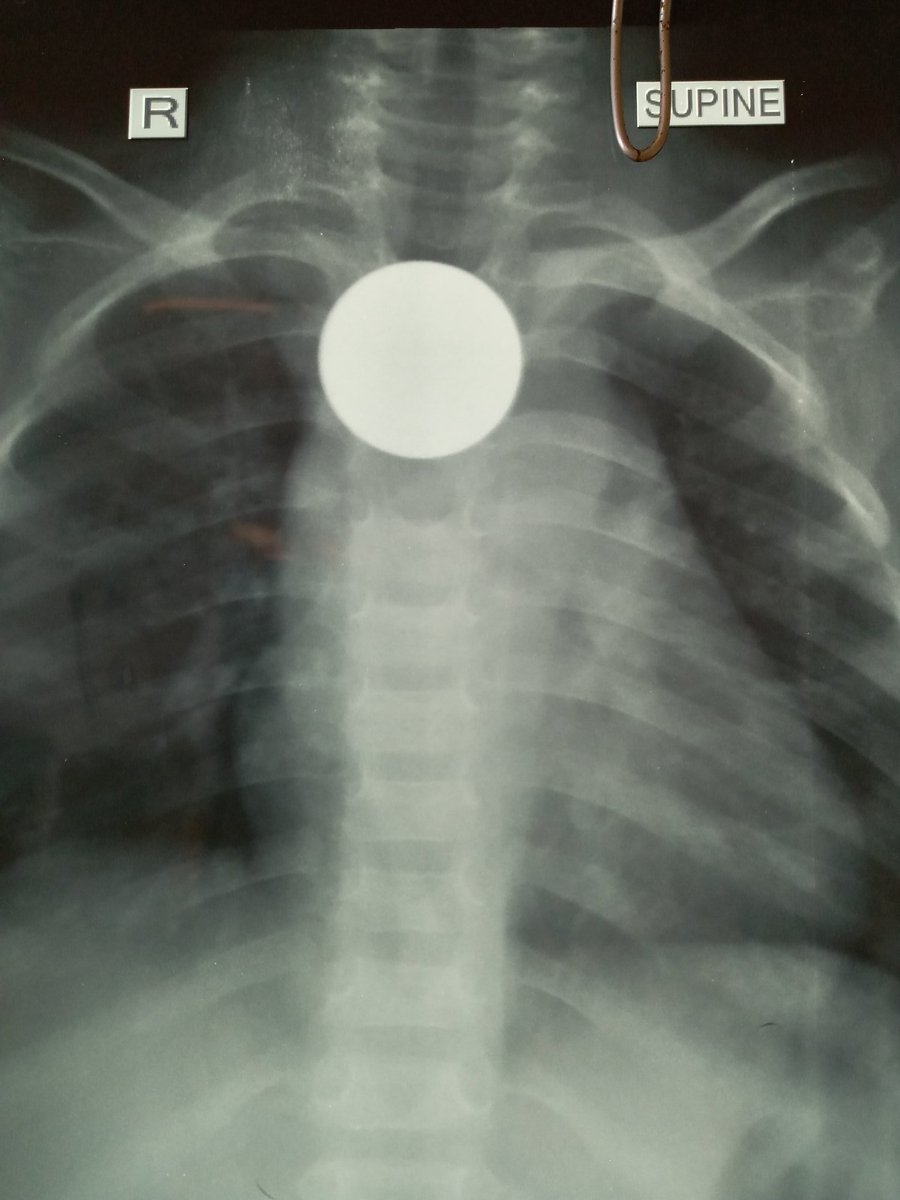

Признаки что ребенок что то проглотил

Признаки что ребенок что то проглотил 108 фотографий